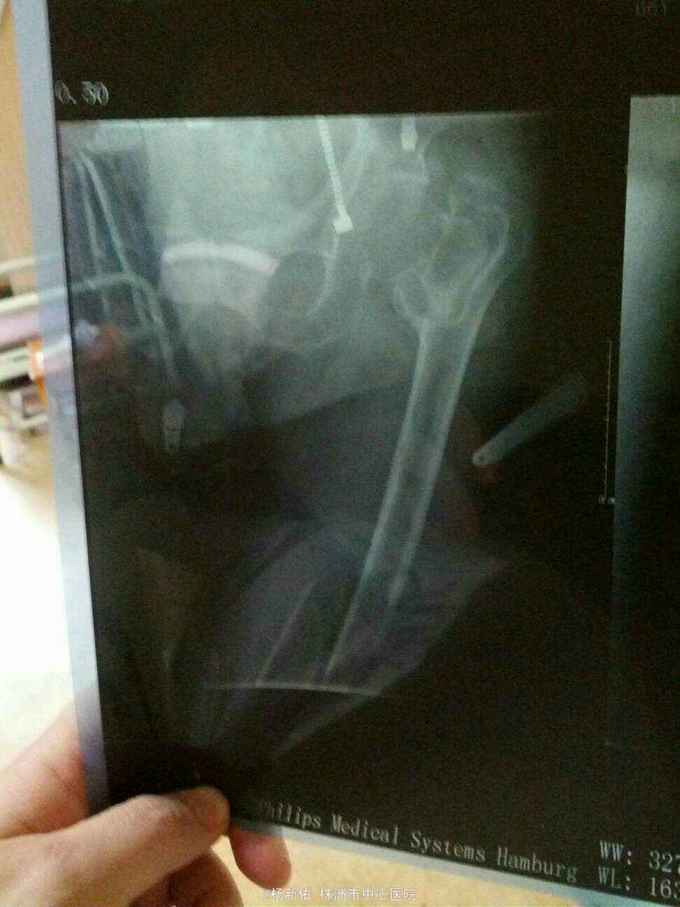

股骨粗隆间骨折并股骨干骨折

骨折 股骨粗隆间骨折 股骨干骨折

意外摔伤左下肢2天入院,2年前外伤至左股骨粗隆间骨折,未做治疗。尿毒症多年,目前透析3次/周

左大腿畸形,反常活动,左髋关节活动受限,

左股骨下段骨折,左股骨粗隆间骨折(阵旧性,骨不连),尿毒症。家属要求手术。

1.手术方式:患者目前有低蛋白血症(白蛋白29),贫血(Hb 66g/L)